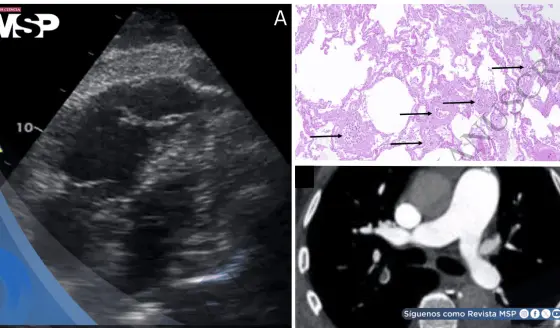

Shock obstructivo agudo por microangiopatía trombótica tumoral pulmonar en paciente con estenosis aórtica